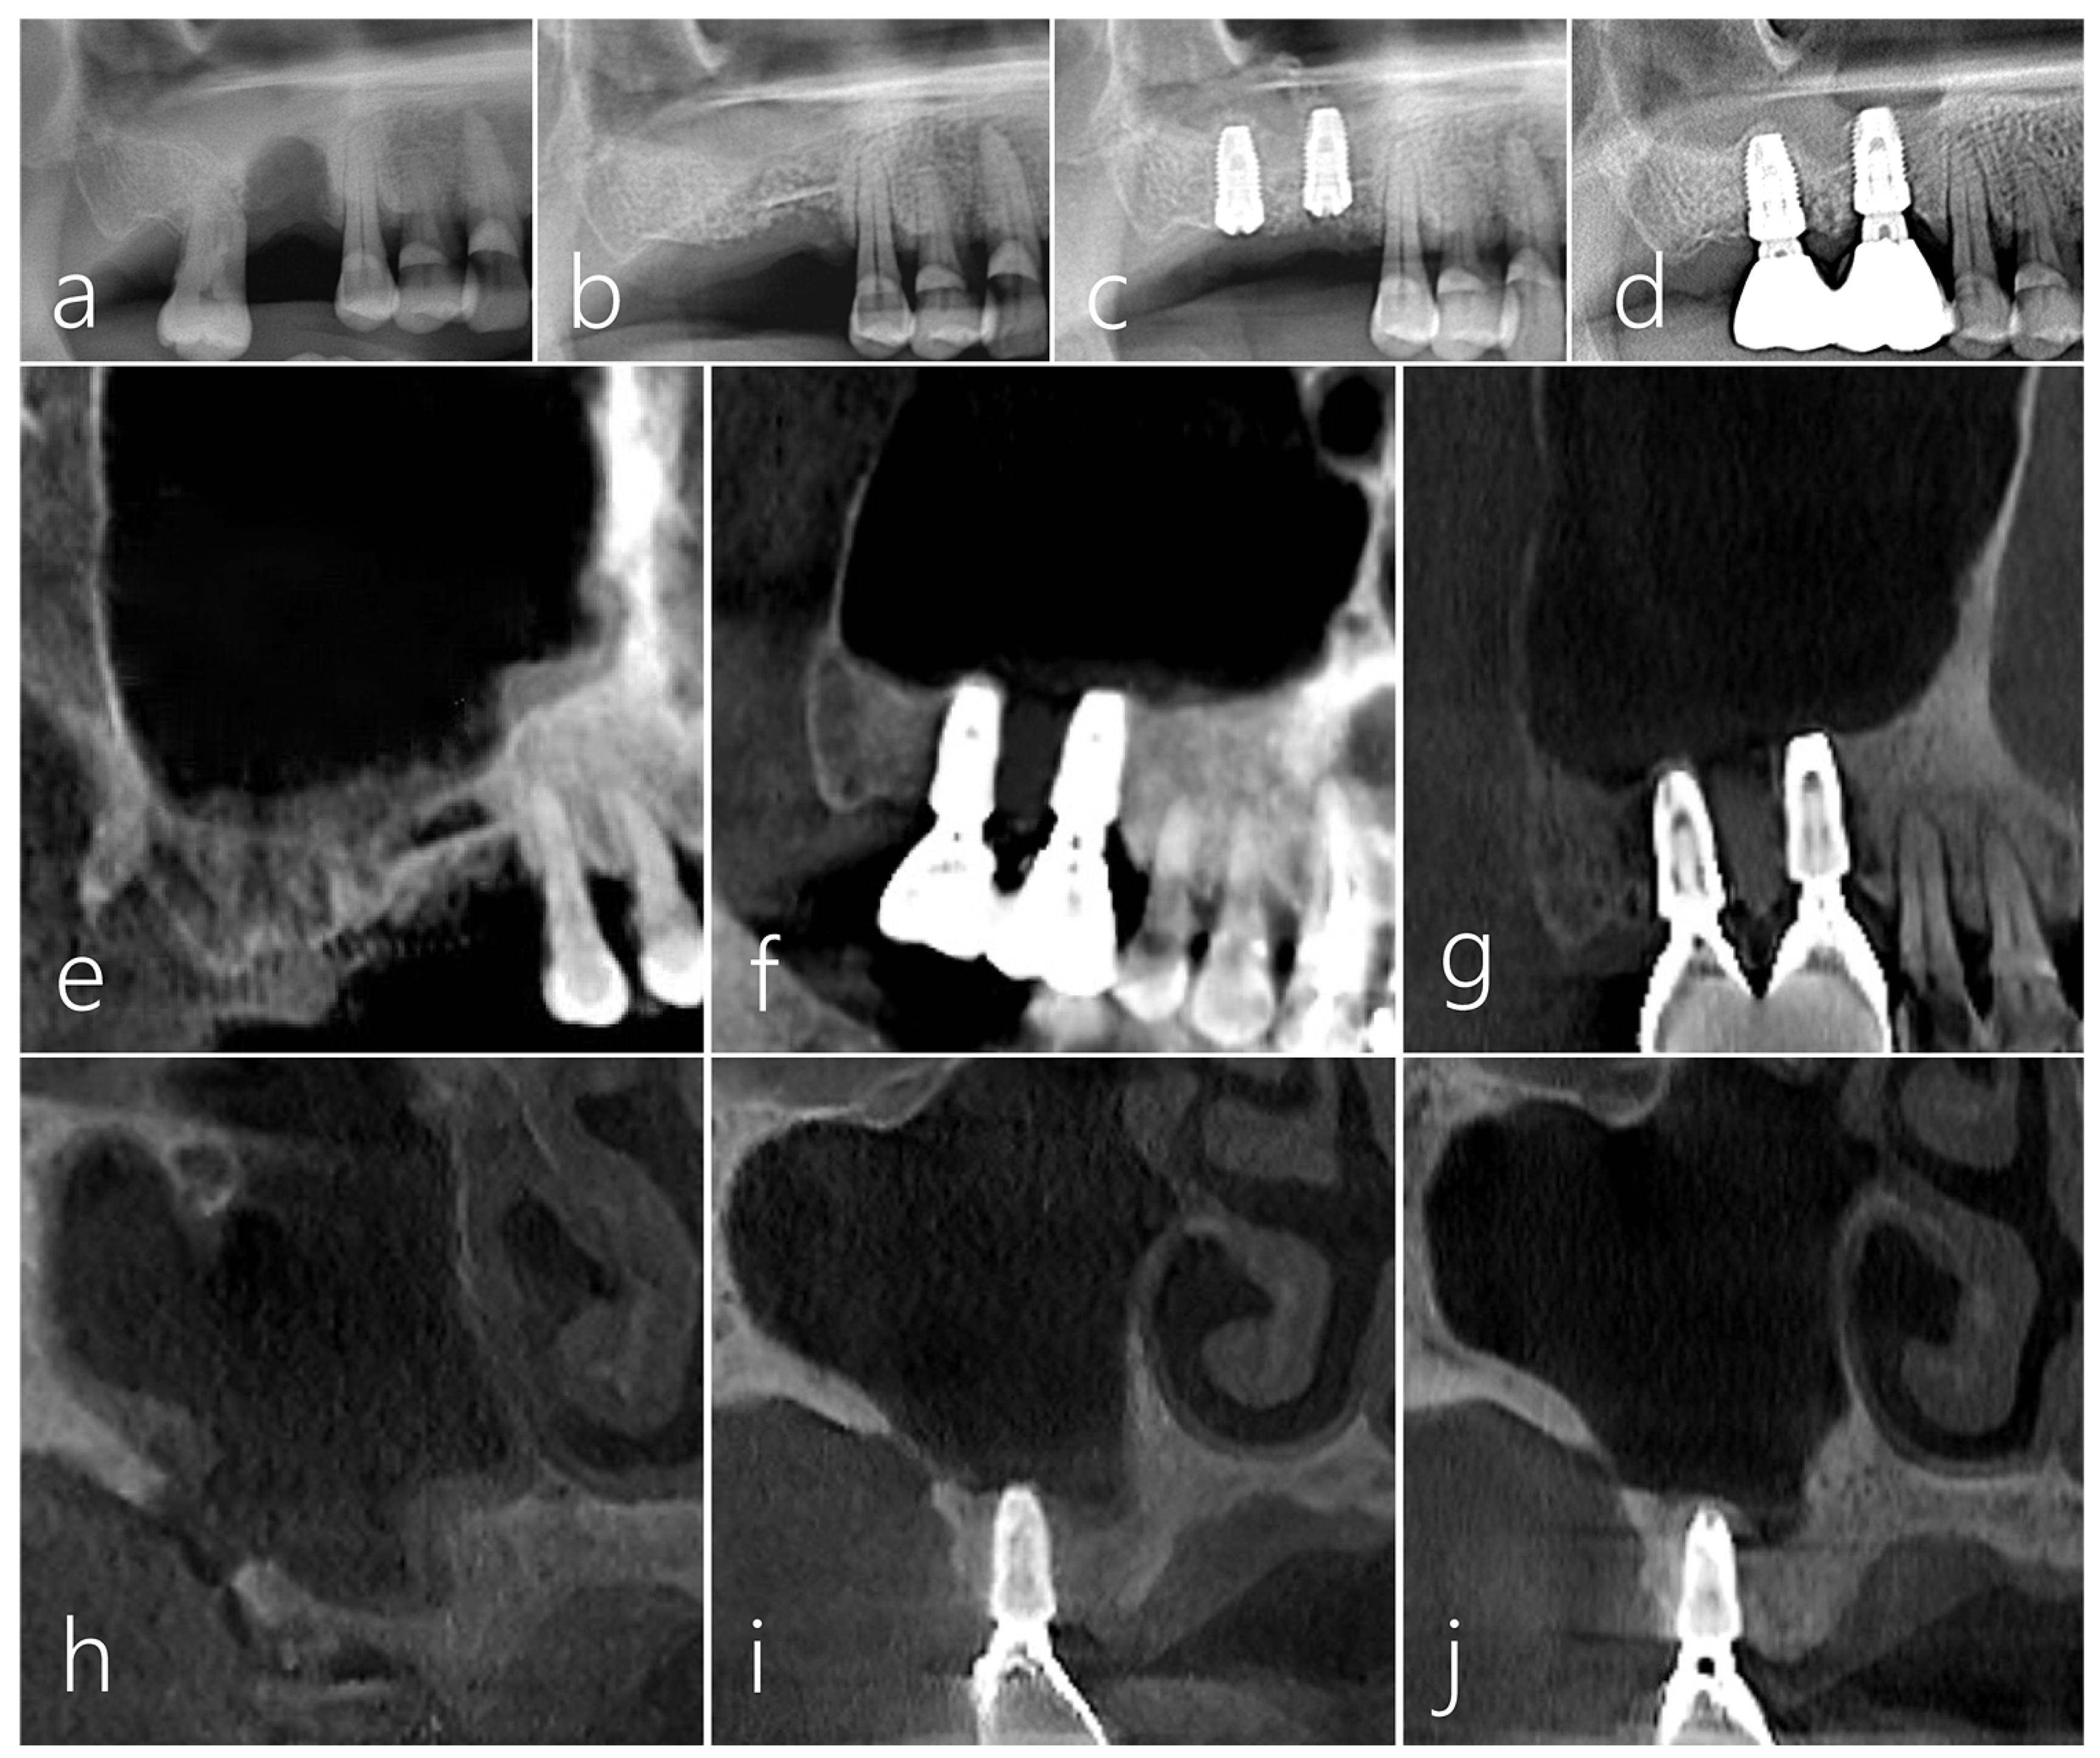

2.3. Case 3

A 61-year-old male non-smoker without significant medical history had #16 extracted 3 months prior and presented a post-extraction socket with a severe vertical ridge deficiency (Figure 8a). The #17 tooth was also extracted, and the bone bridge technique was performed using the lateral bony window of the maxillary sinus along with particulate grafts to prevent any dead space formation (Figure 8b). After 6 months of healing, two Ø 4.3 × 10 mm SLA-textured implants (Implantium, Dentium, Suwon, Republic of Korea) were placed. The bone bridge was well integrated with the adjacent native bone. Uncovering was performed after 4 months, and the prosthesis was delivered after 2 months (Figure 8c). In the panoramic radiograph taken 7 years after prosthesis delivery, the crestal bone level was still well maintained, and the implants were stable (Figure 8d). No abnormal findings were found in follow-up CBCT images (Figure 8e,f). In the sagittal image of CBCT taken 7 years after the prosthesis was delivered, the crestal bone level around the implant was well maintained (Figure 8g). The donor site in the lateral wall of the maxillary sinus was healing with new bone formation to close the communication (Figure 8h–j).

Figure 8.

Case 3. (a) A localized post-extraction socket with severe vertical ridge deficiency was observed on a panoramic radiography taken 3 months after #16 tooth extraction; (b) The patient’s #17 tooth was also extracted, a bone bridge was prepared using the lateral sinus window of the maxillary sinus, and particulate bone was filled to reduce the dead space; (c) Two implants were placed 6 months after surgery. The bone bridge was well integrated with the adjacent native bone. Uncovering was performed after 4 months, and the prosthesis was delivered after 2 months; (d) Vertical bone augmentation of the compromised post-extraction socket was well achieved in the panoramic radiography taken 7 years after prosthesis delivery; (e) Sagittal image of CBCT taken immediately after the bone bridge technique; (f) Sagittal image of CBCT taken after prosthesis delivery; (g) In the CBCT sagittal image taken 7 years after prosthesis delivery, the crestal bone level around the implant was well maintained; (h) In the coronal image of CBCT taken after bone bridge technique, a donor site was observed; (i) The size of the donor site was reduced in the coronal image of CBCT taken after the prosthesis was delivered; (j) Only a small trace of the donor site was observed in the coronal image of CBCT taken 7 years after prosthesis delivery.